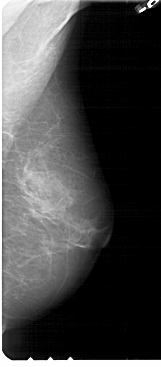

A_1946_1.RIGHT_MLO

RIGHT_MLO LINES 5491 PIXELS_PER_LINE 2401 BITS_PER_PIXEL 12 RESOLUTION 43.5 NON_OVERLAY